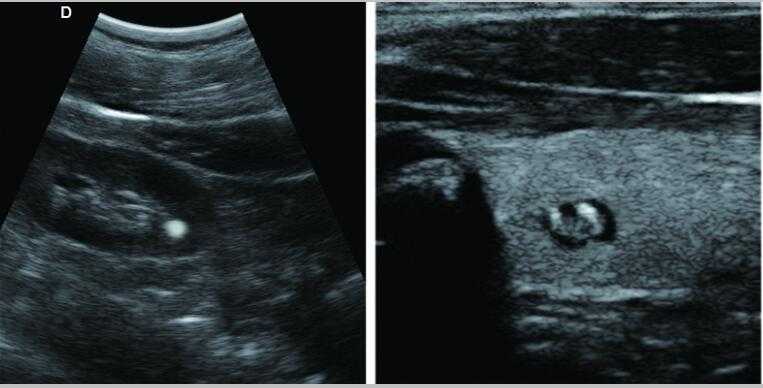

彩色多普勒

采用智能圖像處理技術(shù)1.組織諧波成像技術(shù) 2.噪聲抑制斑點(diǎn)技術(shù) 3.多波束并行處理技術(shù)等

7.應(yīng)用:腹部、婦科、產(chǎn)科、心臟、血管和小器官、泌尿科、肌肉骨骼、兒科等